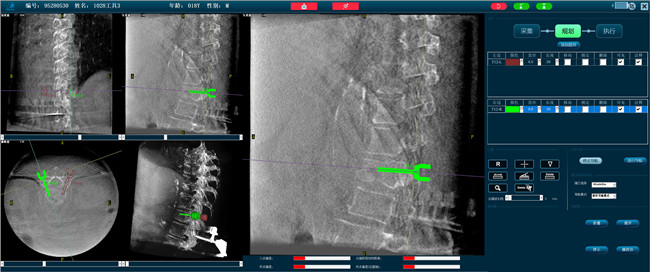

步骤二:手术实施

在病人体表切开一个长1-2cm的创口,沿骨科机器人的机械臂定位点方向将克氏针导向套筒,通过创口送至病灶椎体处,并沿套筒方向打入克氏针进行定位。沿导针插入工作套管,取出导针,完成球囊扩张后,通过骨水泥注入器准确地在骨折部位缓慢注入骨水泥,帮助其恢复椎体的形状和强度。